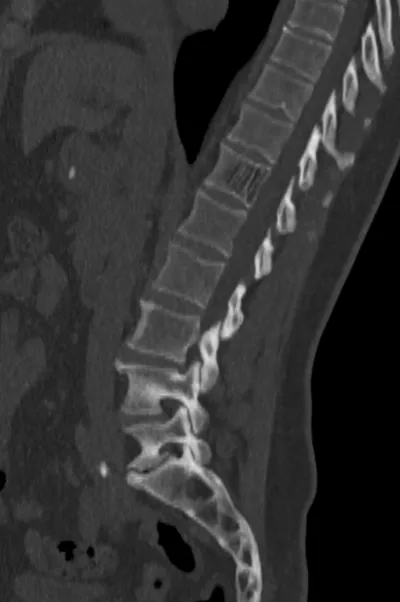

Browse 8 medical images tagged with benign. This collection includes various imaging modalities for medical education and reference.

- This collection contains 8 radiology images related to benign, including various imaging modalities such as X-rays, MRIs, CT scans, and ultrasound images commonly used in medical diagnosis and education.